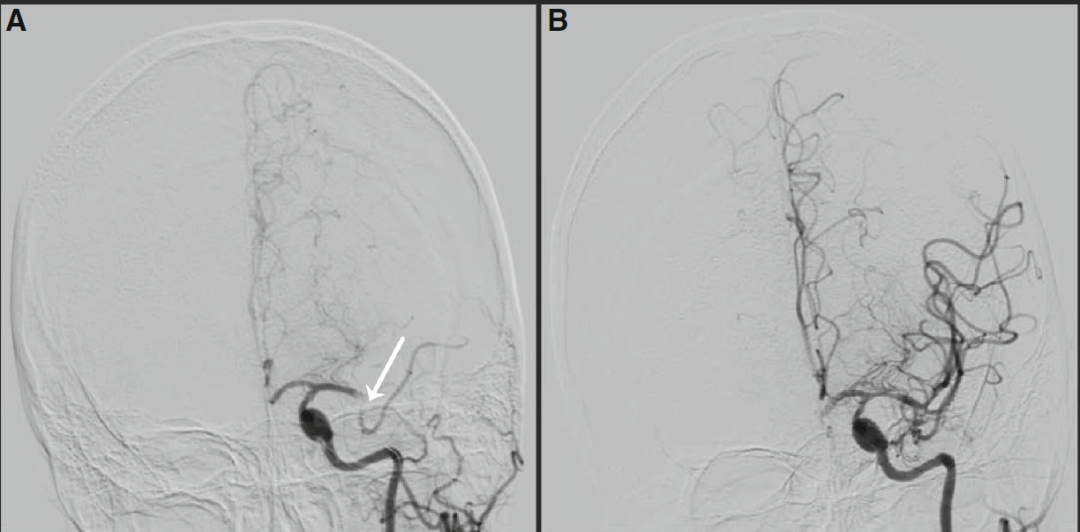

▲图1.

大脑中动脉栓塞的血管造影图像。A.左大脑中动脉堵塞(血管造影)。B. 行血栓抽吸术后,血流恢复。